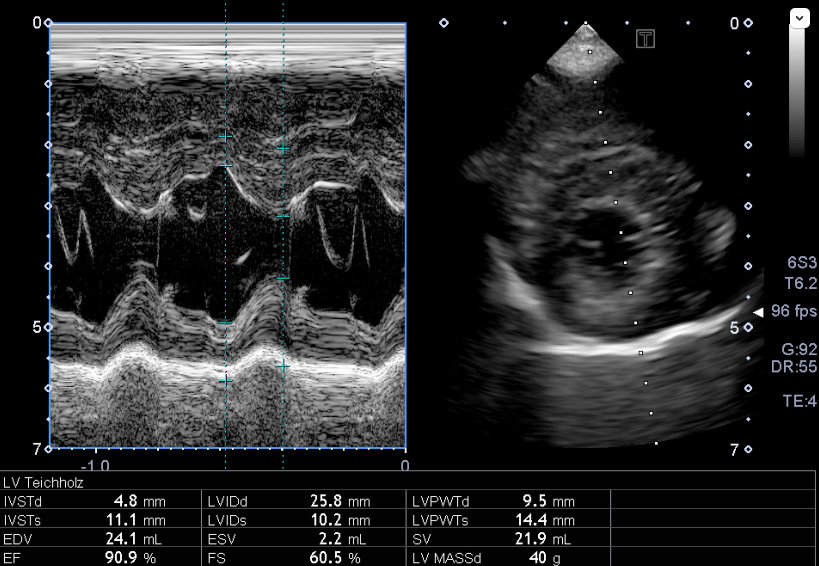

心臓エコー内服開始3年目 フロセミド開始